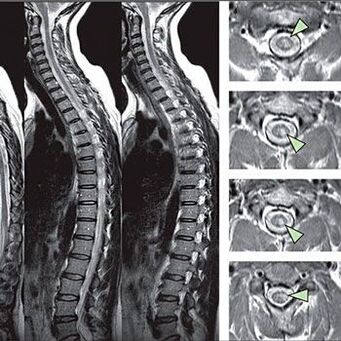

Duyarlılık bozuklukları belirtilerini belirlemek için özel fonksiyonel testler yapılır. Enstrümantal yöntemlerden en bilgilendirici teşhis seçeneği bir X -Ray'in performansıdır. Bununla birlikte, omurga üzerinde kapsamlı bir çalışma için, MRI ve BT genellikle gerçekleştirilir. Kardiyovasküler sistemin hastalıklarından şüphelenmesi durumunda, hastanın EKG prosedürüne geçmesi önerilir.